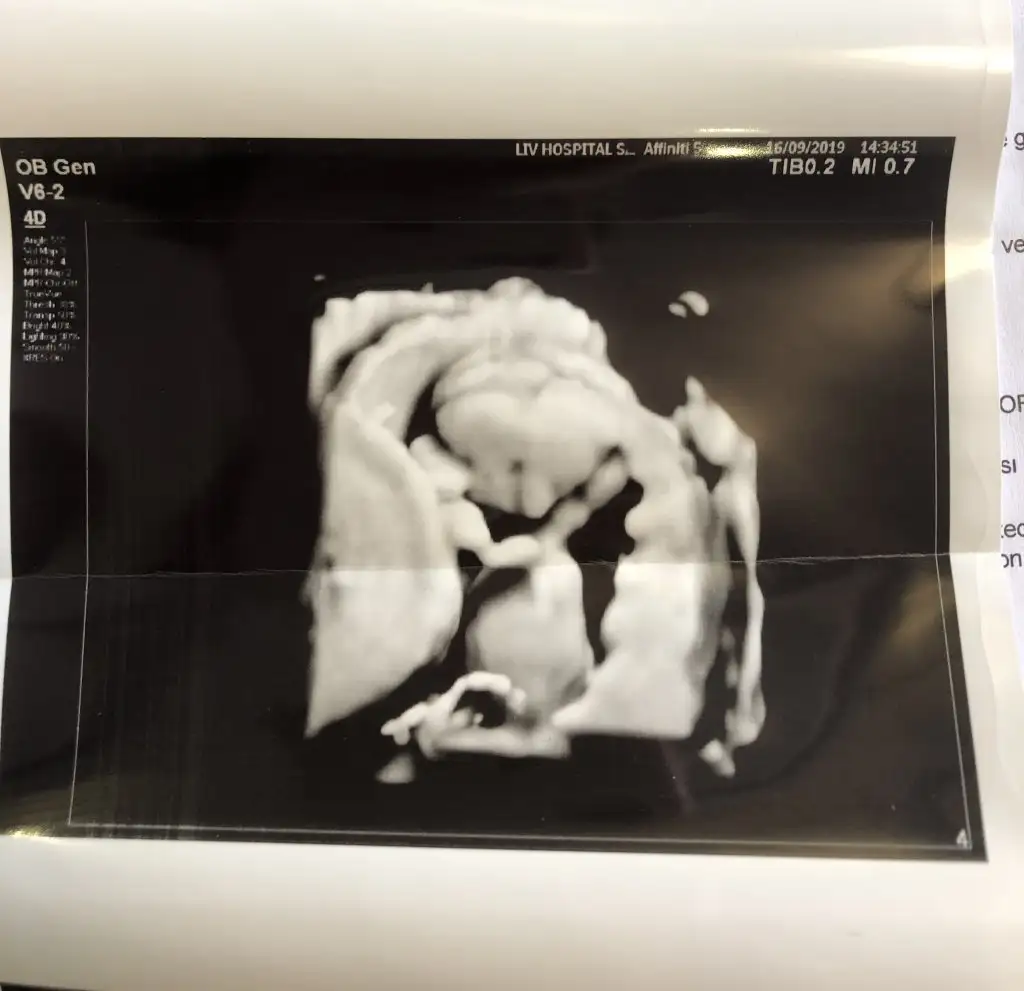

Kendim gecmise donup yorum yaptiklarima bakiyorum ve onlarin kesinlesen cinsiyetlerine sende dene tek tek sormaktan iyidir bazilarida ozelden msj atiyor tahmininiz tuttu diye canim hamilelik sicaklarda cok zorlasada iyi gidiyor simdilik 25 haftalik olduk cok sukurKız tutanlar yazmasa nerden bilecen 10 da 7 si tuttugunu bak yazmıyor diyorsun her neyse tatlım doguma ne kaldıkaç haftalık oldunuz guzel anne

Yorumum kızdı ögrrndinizmi10+4 deyiz kızlar tahmin alabilirmiyim